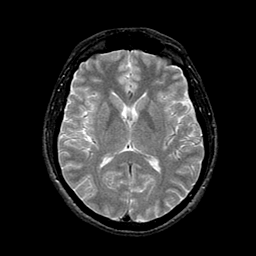

AIDS dementia: overlay -- Slice #9

[Home][Help][Clinical][Tour 1] Slice 9